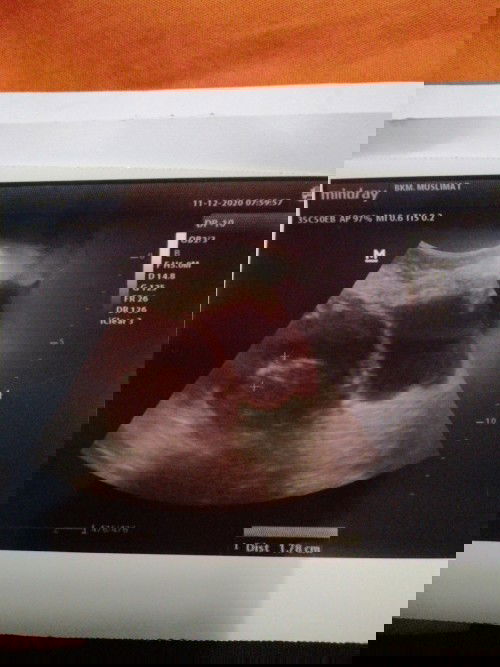

Assalamualaikum.. Bund.. Ini hasil USG ku yg kedua... Prediksinya sdh 11 W.. Adakah bunda yg punya pengalaman sprti saya.. Perut atas yg mmbesar.. Krn saya juga orgnya gemuk... Dan saya juga ngalami trauma dg kehamilan sblmnya prnh kgguran d usia kurleb 8w.. Bgm cara ngilain rasa trauma tsbt.. #seriusnanya